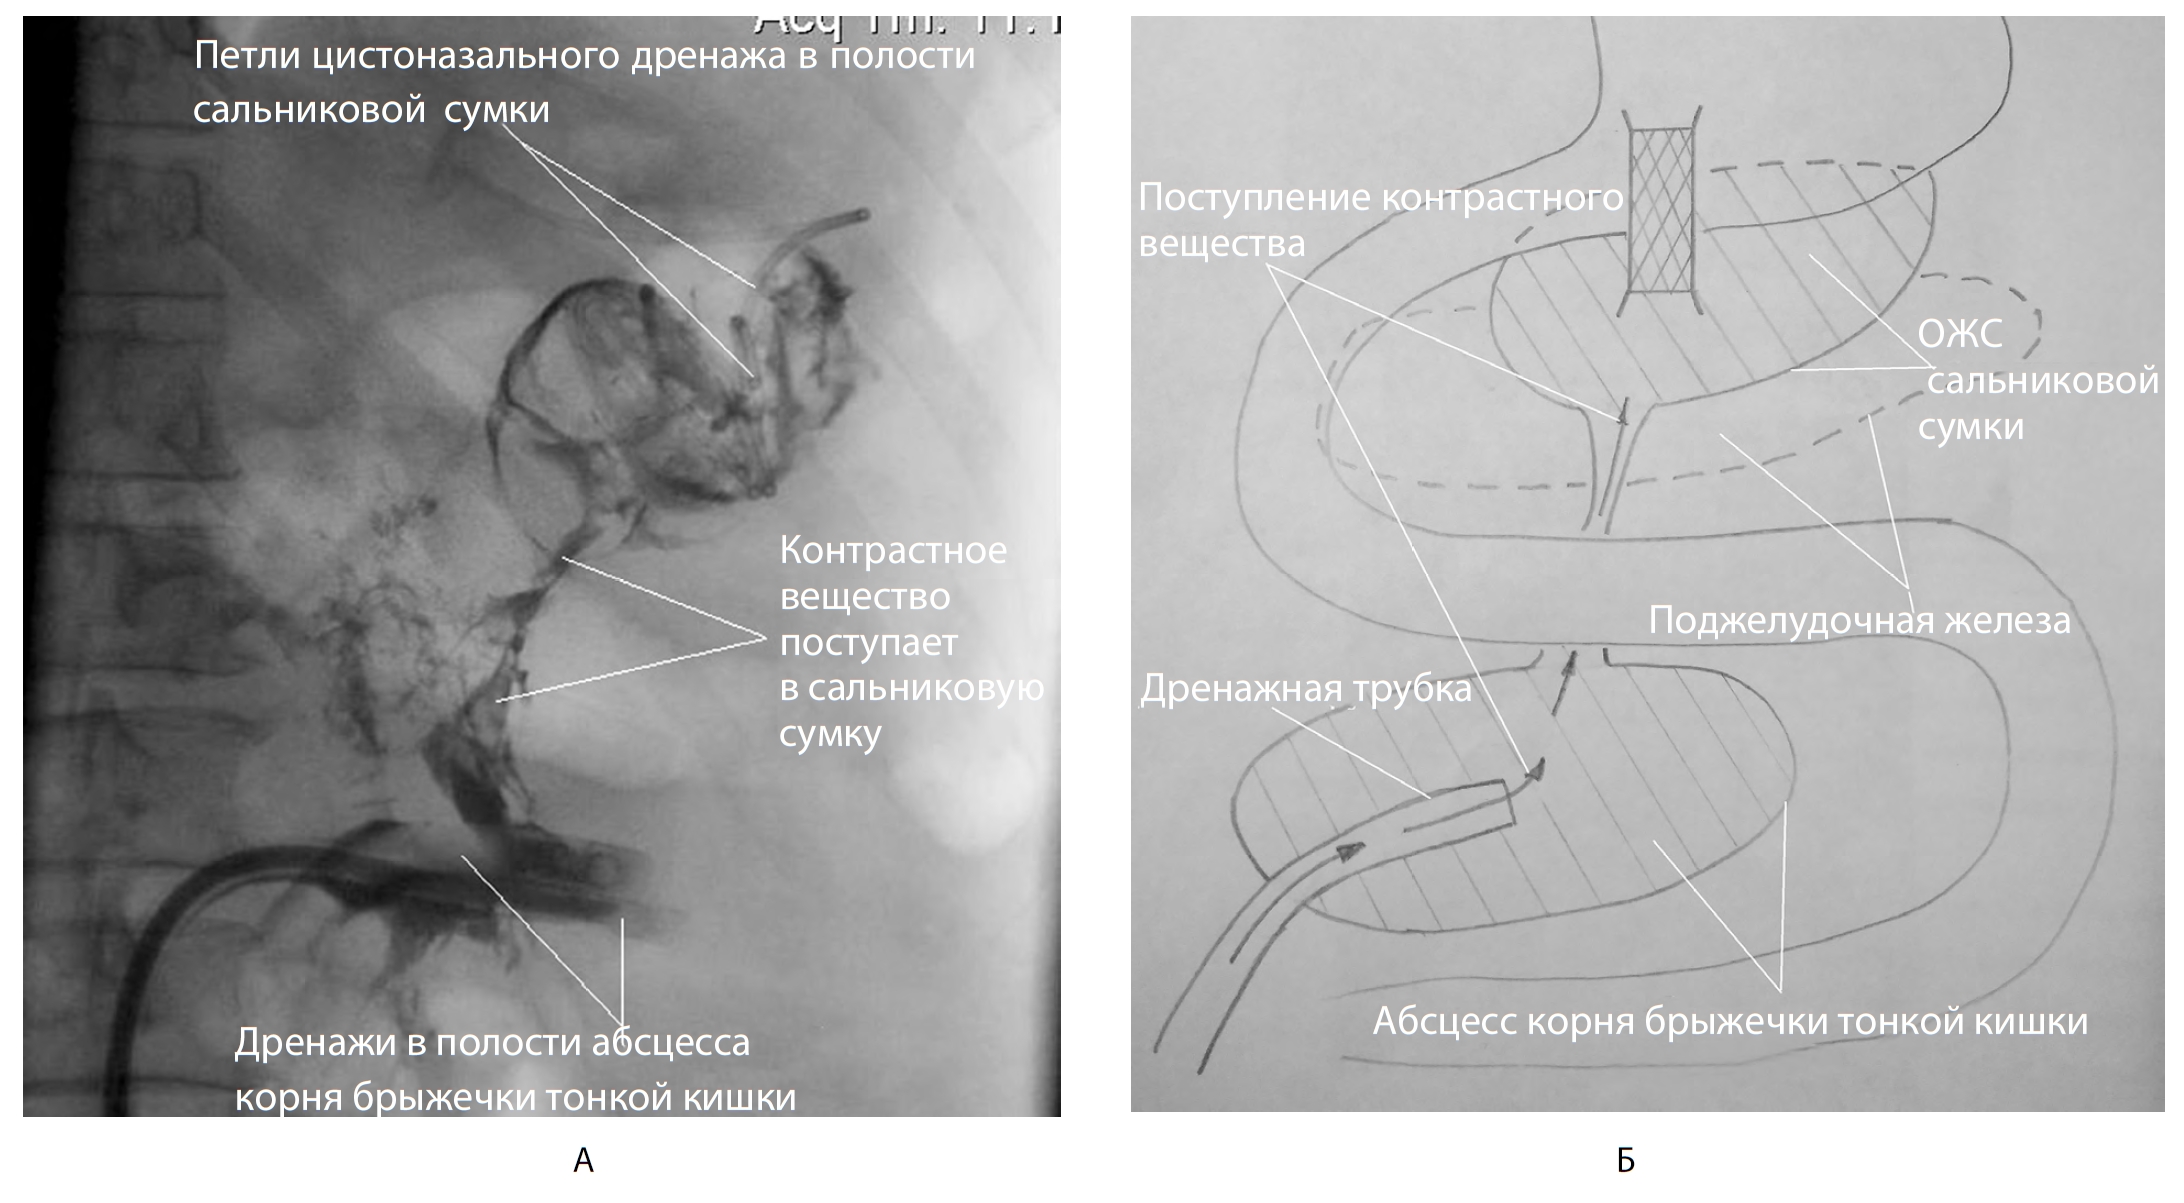

При выполнении рентгеноконтрастного исследования выявлено сообщение сальниковой сумки с полостью абсцесса брыжейки тонкой кишки (рис. 11).

Рис. 11. Контрольное рентгеноконтрастное исследование на 56-е сут болезни. А — рентгенофистулография; Б — схема сообщения полостей

В дальнейшем проводились этапные эндоскопические секвестрэктомии на фоне активного промывания полостей абсцесса брыжейки тонкой кишки и сальниковой сумки раствором хлоргекседина через дренажные трубки (рис. 12).